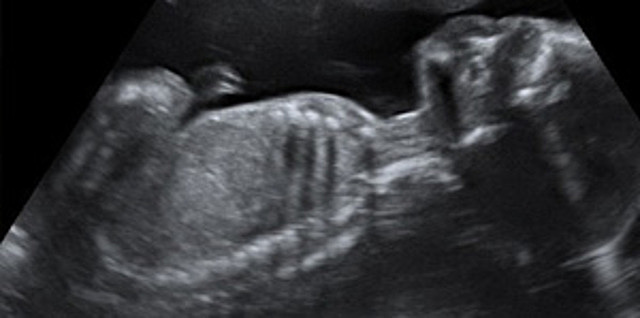

Como sigue teniendo espacio en el útero para flotar y moverse, está bastante activo y coordina cada vez mejor sus movimientos. En las ecografías se le puede ver “pedalear” con las piernas y presionar con los pies la pared uterina. Los puños también tienen más fuerza y puede coger el cordón.

• Semana 27

Semana 27

El bebé es bastante delgado aún, aunque a partir de ahora acumulará más grasa y aumentará de peso considerablemente. La longitud desde la coronilla hasta las nalgas sería de unos 24 centímetros (alrededor de 36 centímetros en total), y el peso se sitúa cerca de alcanzar un kilogramo.

A partir de esta semana existen más posibilidades de que el bebé sobreviva si nace prematuro. Pero quedan 13 semanas para llegar al término del embarazo, por lo que sigue desarrollándose.